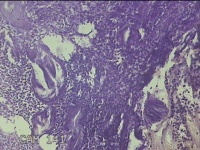

宫腔内容物

性别

女

年龄

45岁

临床诊断

子宫内膜息肉

一般病史

月经量增多10年,B超检查发现宫腔异常回声半月余。

标本名称

大体所见

灰白暗红色不规则碎组织1.5x1.3x0.7cm一堆。

图3